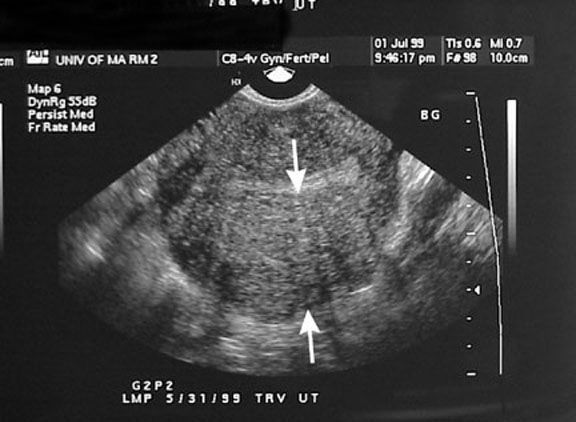

«Большими» признаками эндометриоза при УЗ- диагностике являются:

- шарообразная форма матки (в норме быть грушевидная);

- матка увеличена в размерах.

- разная толщина передней и задней стенок матки (должна быть примерно одинаковая);

- неоднородный мышечный слой («звездное» небо или по типу «булыжной» мостовой).

фото взято из открытого источника сети "Интернет".